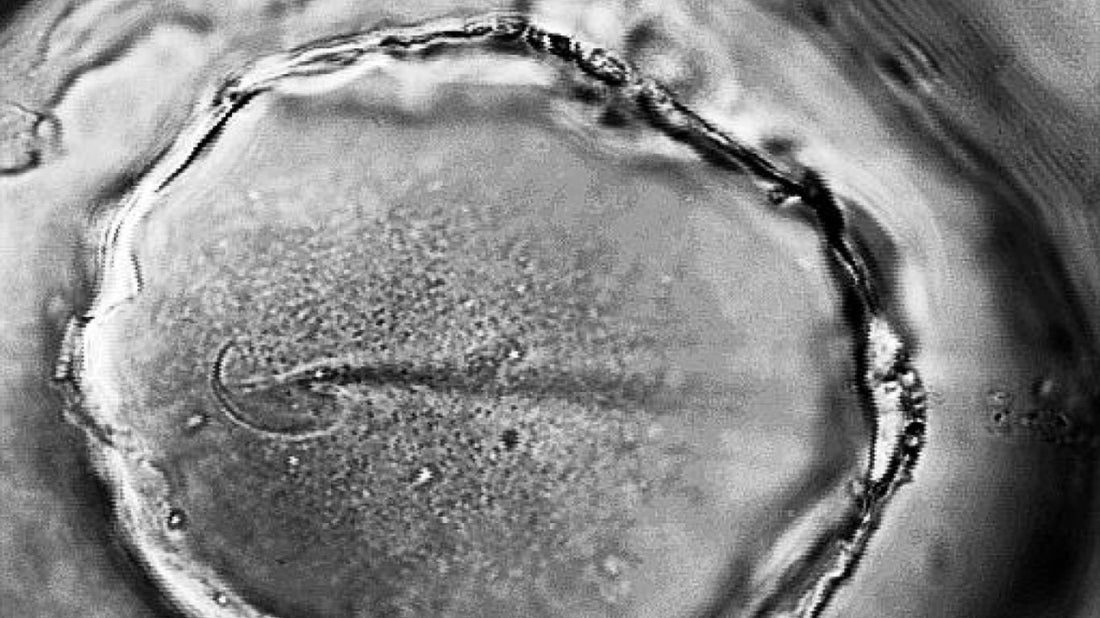

Comment définit-on une bonne qualité ovocytaire ? La qualité ovocytaire désigne la capacité d’un ovocyte (ou ovule) à être fécondé, à se diviser correctement et à donner un embryon viable. C’est l’un des facteurs clés de la fertilité féminine au même titre que l’ovulation ou la réserve ovarienne. Un ovocyte de bonne qualité possède un matériel génétique intègre, une bonne fonction mitochondriale, un équilibre oxydatif optimal ce qui lui confère la capacité de développer en embryon sain. La qualité ovocytaire dépend de plusieurs paramètres : l’âge : → La qualité ovocytaire diminue progressivement à partir de 35 ans. le stress oxydatif : → Les radicaux libres endommagent l’ADN ovocytaire. l’état inflammatoire chronique : → La présence de pathologie comme l’endométriose, le SOPK.. les troubles métaboliques : → L’insulinorésistance (SOPK), les carences nutritionnelles. l’environnement → L’exposition à des perturbateurs endocriniens, la pollution, la consommation de tabac, d’alcool, de drogues.. → La qualité du sommeil, du microbiote intestinal et la gestion du stress. On ne peut pas créer de nouveaux ovocytes mais on peut améliorer leur développement pendant les 3 mois qui précèdent l’ovulation. C’est durant cette phase de maturation folliculaire que les ovocytes sont les plus sensibles aux apports nutritionnels, hormonaux et environnementaux. Comment peut-on améliorer la qualité ovocytaire ? Pour soutenir la qualité ovocytaires il existe plusieurs solutions : une supplémentation en myo-inositol (pour l’équilibre hormonal), en Folates (avec de la vitamine B9 active!), en vitamine B12, en Zinc, en iode, en vitamine D et en antioxydants (telle que la vitamine E ou la vitamine C) la gestion du stress un sommeil réparateur une activité physique douce (yoga, pilates, marche, natation… ) une réduction de l’exposition aux toxiques (tabac, alcool, drogues…)